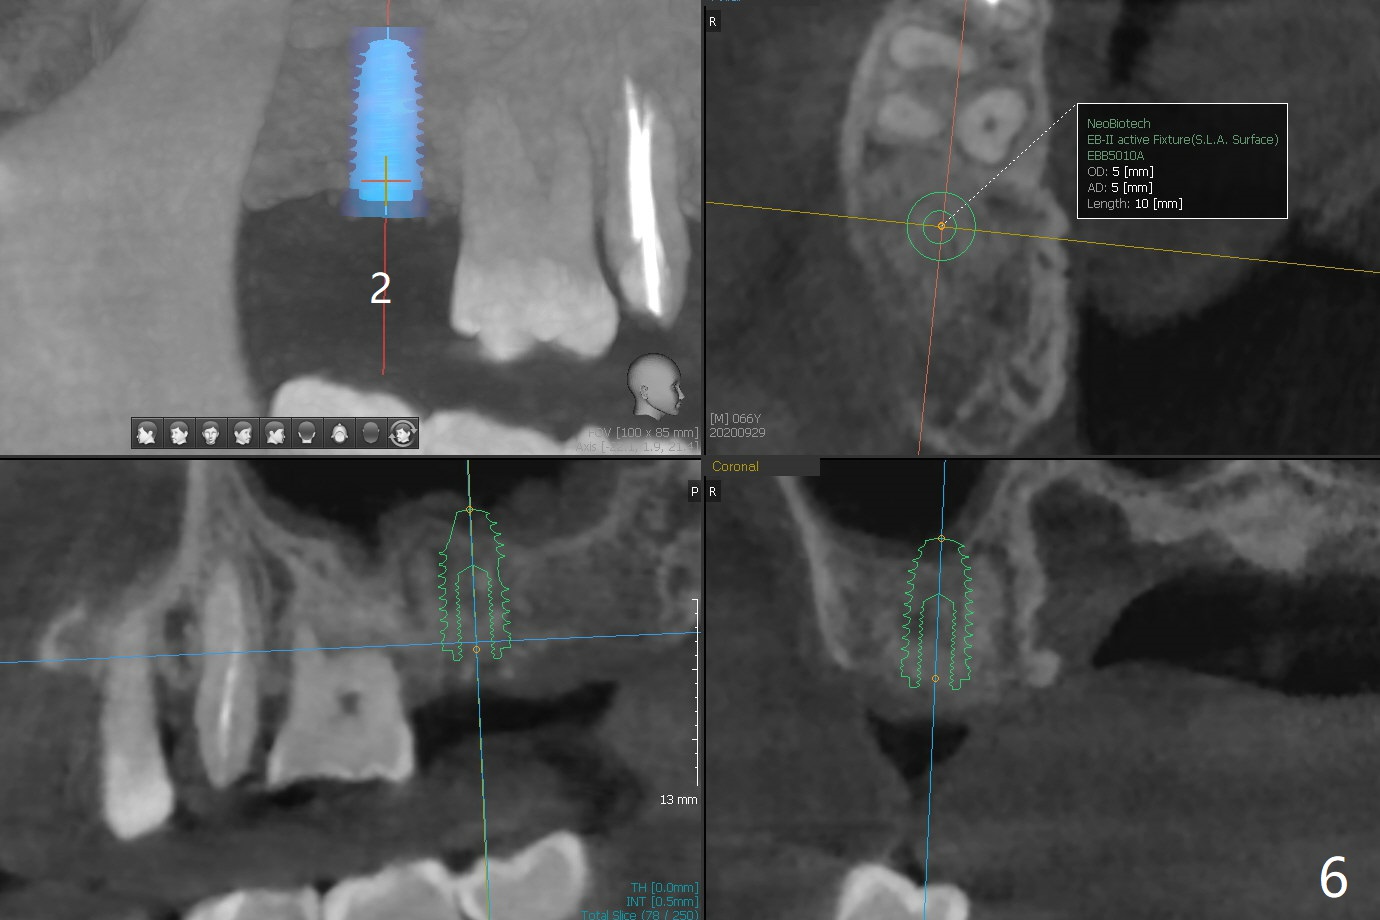

The apices of the mesio-buccal (MB) and disto-buccal (DB) roots are soft when the tooth #2 is extracted. After socket debridement, there is no air leak. Minera-lized cortical and cancellous mix (50/50) hydrated with ~ .25 ml of .3 mg/ml of rhPDGF-BB is placed in MB and DB sockets and pushed upward with a curette. Finally the whole socket is filled up to the crest and a piece of 8x8 mm BioXclude is placed and sutured in placed with 4-0 PGA (Fig.1-3). In fact sinus lift is accomplished moderately MB and DB (Fig.2,3). In fact the density of the bone graft 6 months postop remains the same as immediate postop, similar to the native bone as well (Fig.4,5). With socket preservation, a longer implant will be placed at #2 (Fig.6, as compared 8.5 mm at #15 without bone graft).